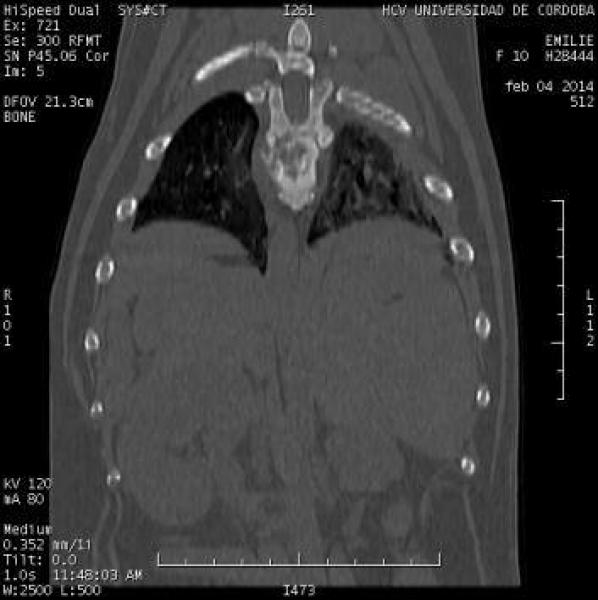

Neoplasia vertebral